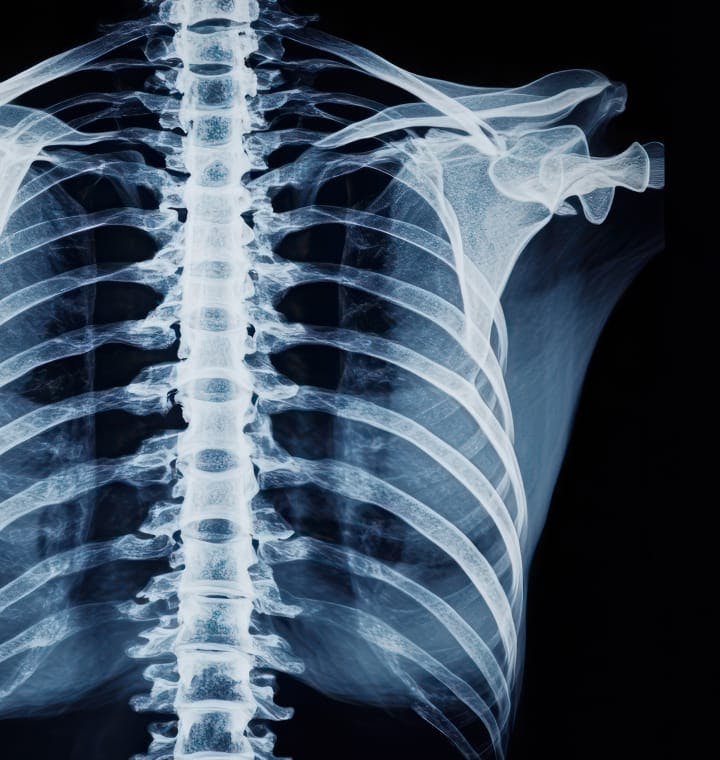

Prior to the procedure, your treatment area is thoroughly cleaned and prepped, and a local anesthetic is applied to minimize discomfort. Under live fluoroscopic (X-ray) guidance, Dr. Stieber carefully inserts a fine needle into the epidural space—the area just outside the dural sac that contains your spinal fluid and nerve roots. Contrast dye may be injected to confirm accurate placement. Once the needle is in position, a measured dose of corticosteroid is slowly injected, diluting inflammation and alleviating nerve compression. The entire process typically takes between 30 to 45 minutes, after which you are monitored briefly before being discharged home, often on the same day.